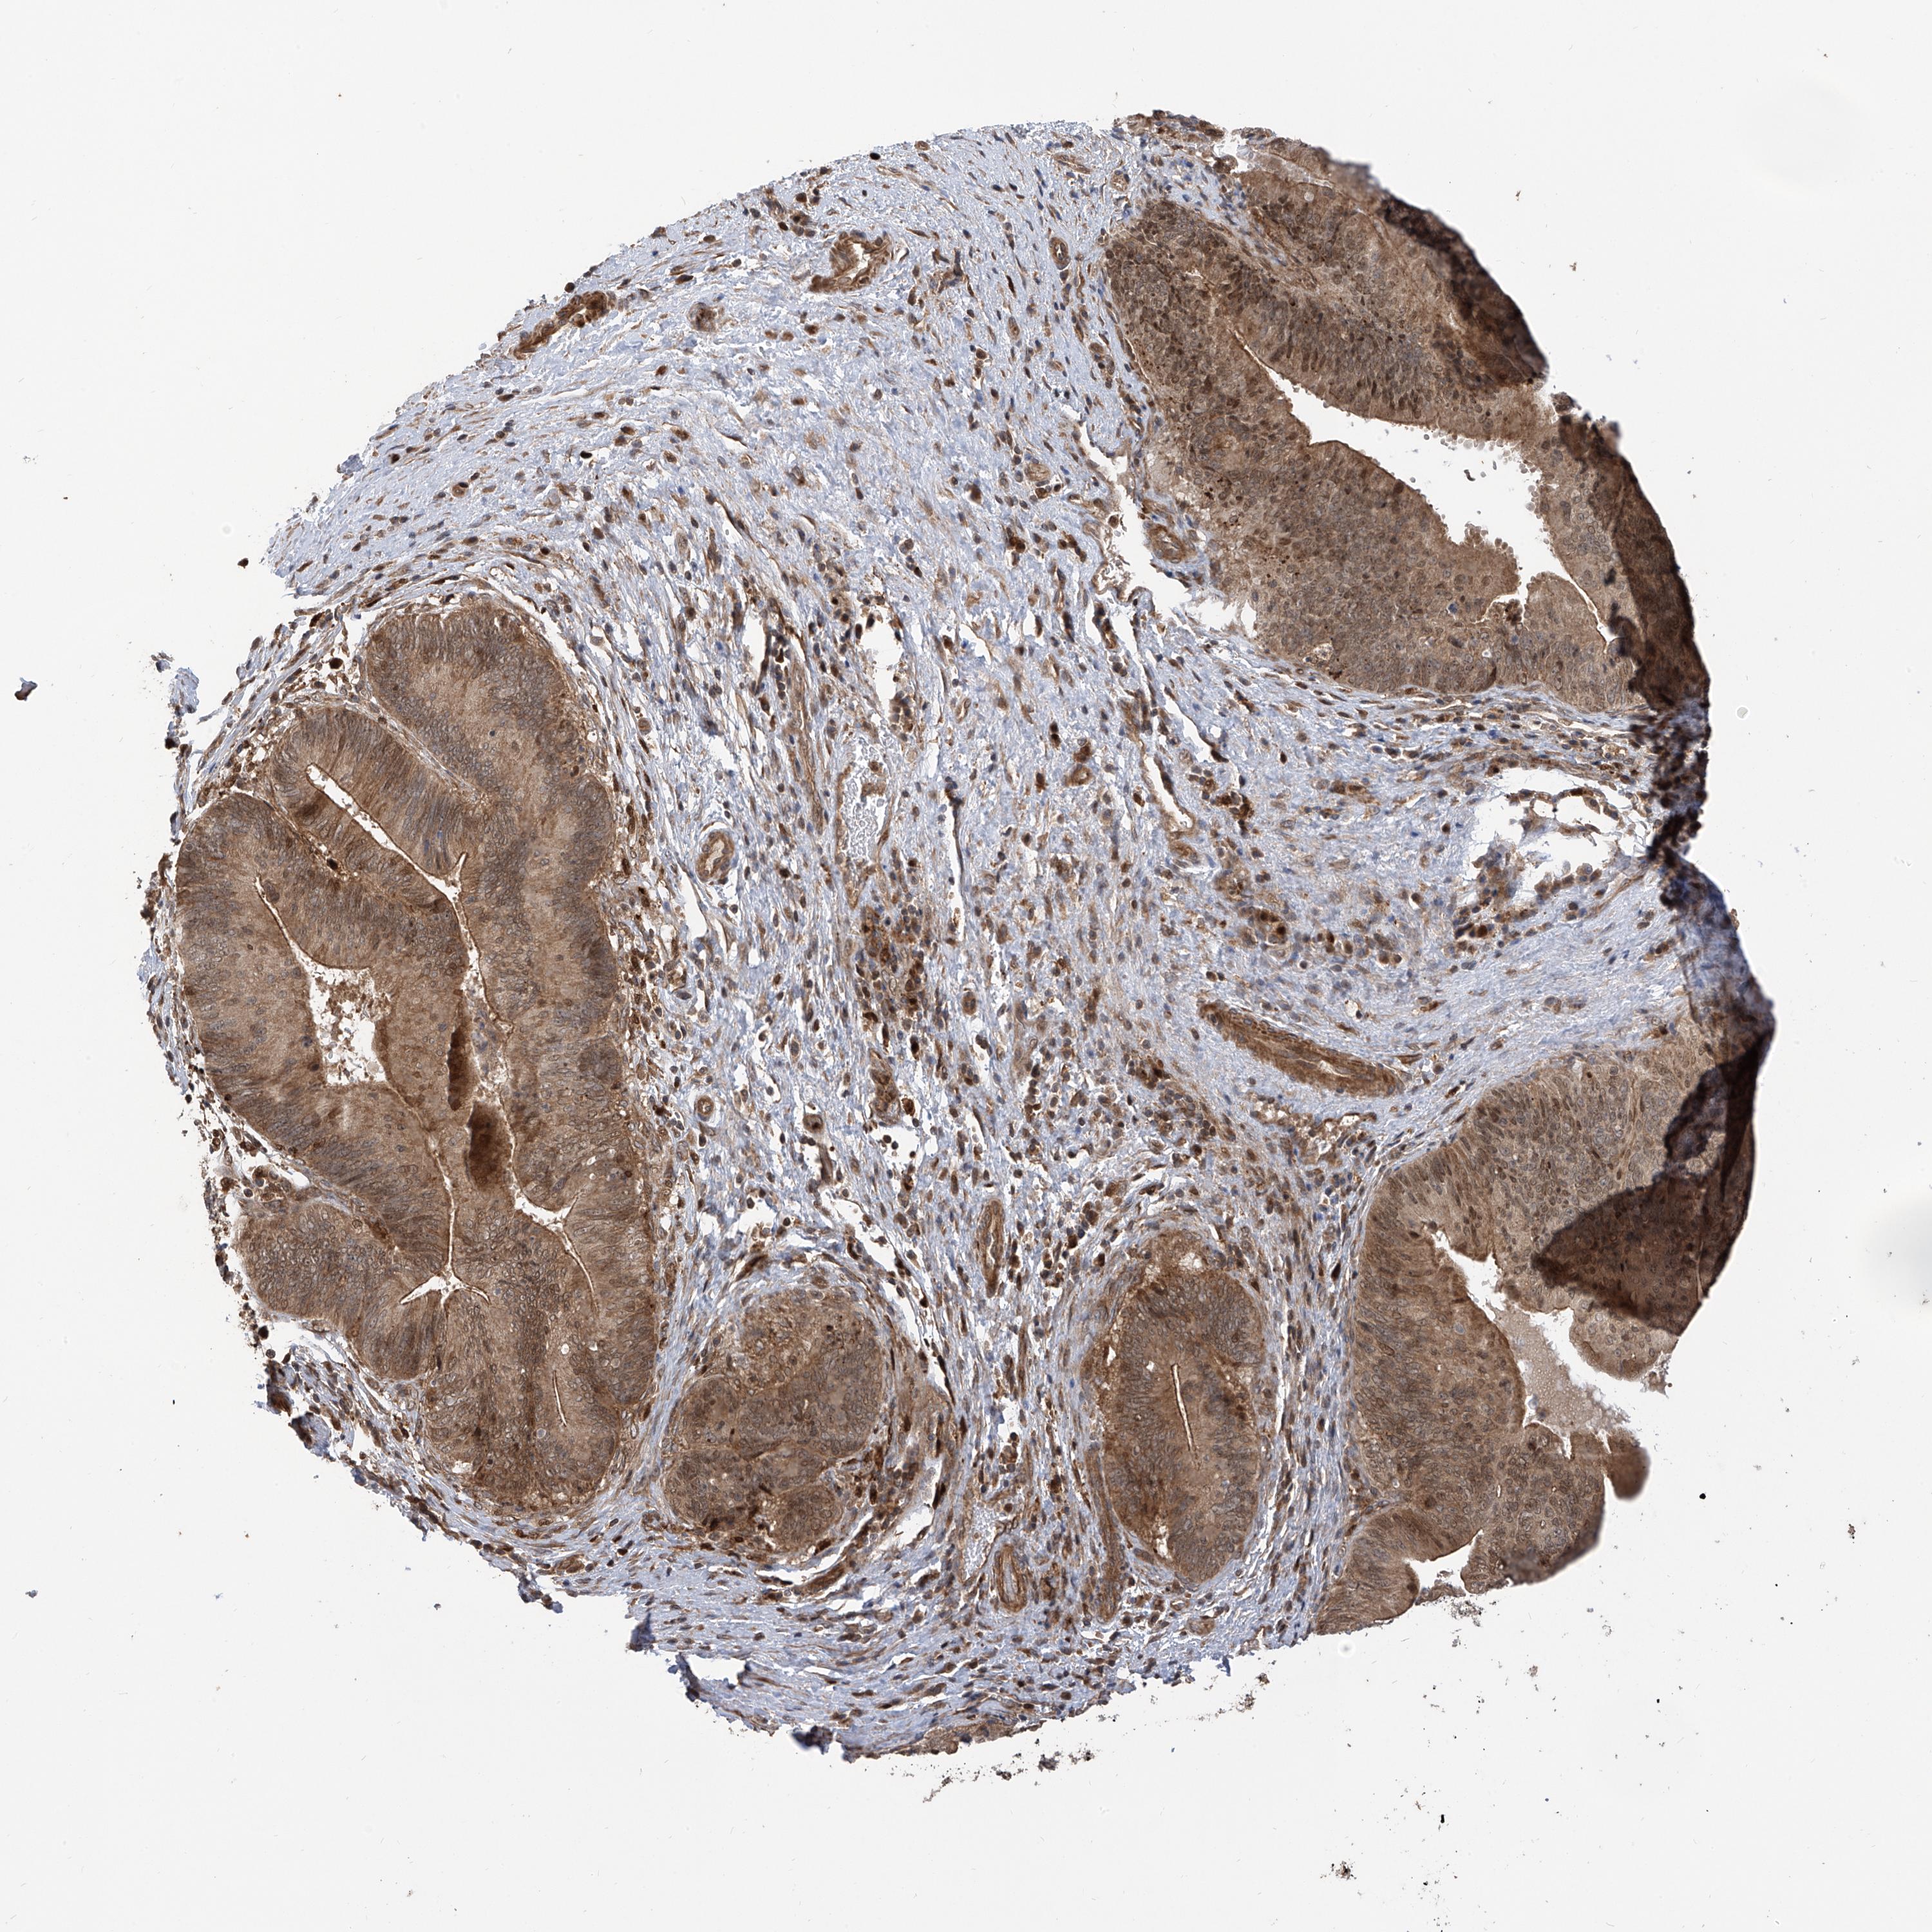

PANCREATIC CANCER - Protein expressioni

A mouse-over function shows sample information and annotation data. Click on an image to view it in a full screen mode. Samples can be filtered based on level of antibody staining by selecting one or several of the following categories: high, medium, low and not detected. The assay and annotation is described here.

Note that samples used for immunohistochemistry by the Human Protein Atlas do not correspond to samples in the TCGA dataset.

Antibody stainingi

Antibody staining in the annotated cell types in the current human tissue is reported as not detected, low, medium, or high, based on conventional immunohistochemistry profiling in selected tissues. This score is based on the combination of the staining intensity and fraction of stained cells.

Each image is clickable and will lead to virtual microscopy that enables deeper exploration of all samples and also displays staining intensity scores, fraction scores and subcellular localization as well as patient and tissue information for each sample.

Antibody HPA034555

Staining

High

Medium

Low

Not detected

Intensity

Strong

Moderate

Weak

Negative

Quantity

>75%

75%-25%

<25%

None

Location

Nuclear

Cytoplasmic/membranous

Cytoplasmic/membranous,nuclear

Adenocarcinoma, NOS